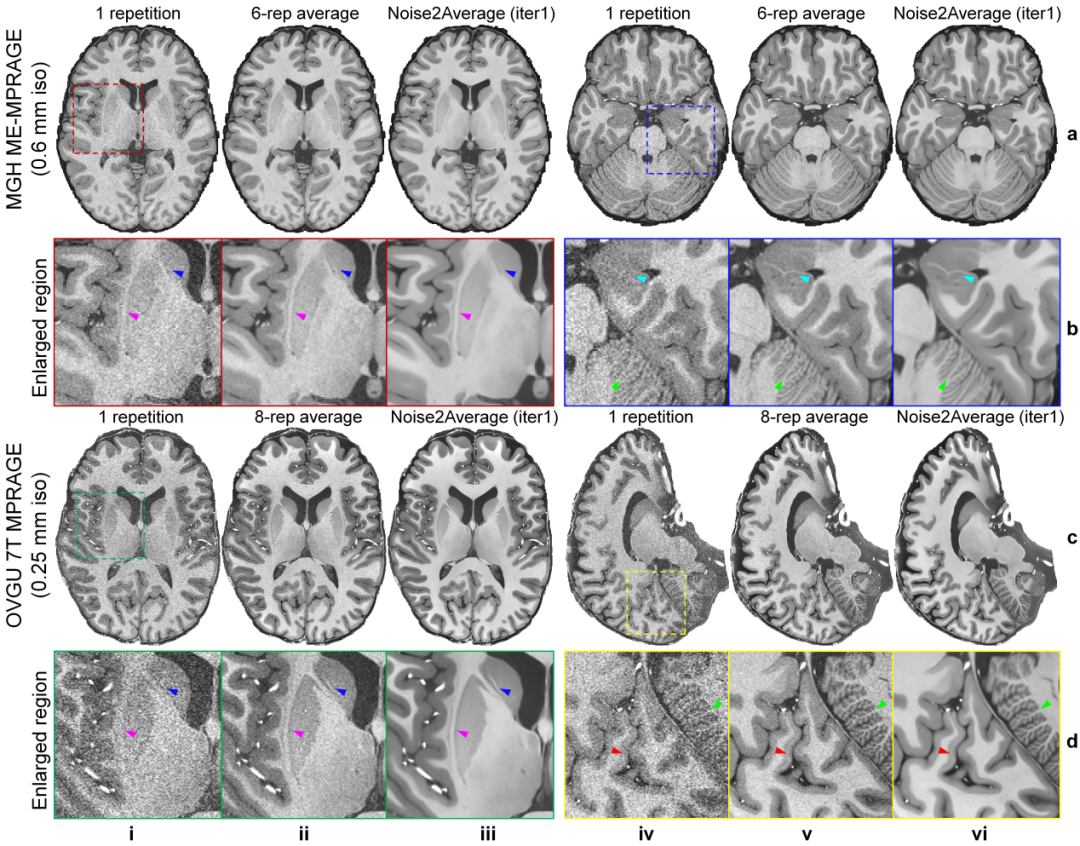

该研究进一步展示了 Noise2Average 在极高分辨率结构成像中的卓越性能。它成功突破了信噪比瓶颈,清晰复原了脑精细解剖结构,提高了即便在传统长时程采集(八小时)下也难以清晰观察的微小结构的可见性。

增强屏状核、尾状核-豆状核灰质桥、热纳里氏线及小脑皮层等精细结构成像